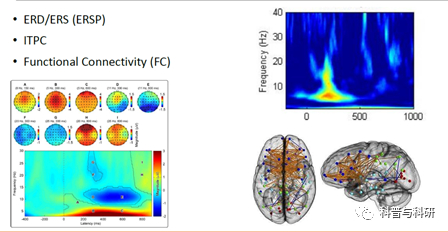

l事件相关同步和去同步(ERD/ERS) l短时傅里叶变换与小波变换 l时频分析操作(Fieldtrip) l时频常见指标提取和绘图 |

功能连接 |

l图论分析概述 l图论的构建 l脑电中常用的图论指标 l图论分析工具包BCT的使用 |